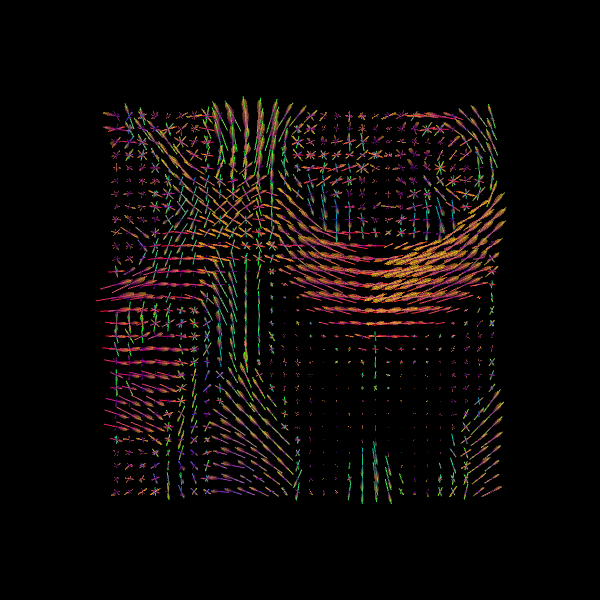

We now visualize both the ODFs and peaks in the same space.

fodf_spheres.GetProperty().SetOpacity(0.4)

scene.add(fodf_spheres)

window.record(scene=scene, out_path="csd_both.png", size=(600, 600))

Image("csd_both.png")

../_images/9074060ddb34e03025e6ef30e9b7d968c7fd48464caf8bdb1f35c0b11e2fad26.png